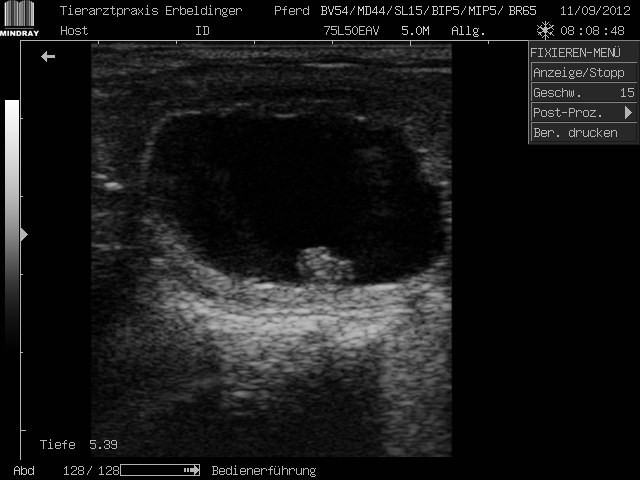

16. Tag einer Trächtigkeit